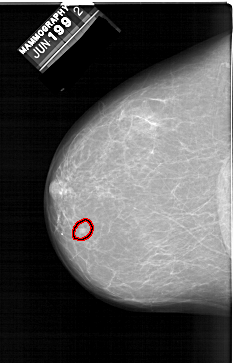

A_1398_1.LEFT_CC

LEFT_CC LINES 6526 PIXELS_PER_LINE 4201 BITS_PER_PIXEL 12 RESOLUTION 43.5 OVERLAY

FILE: A_1398_1.LEFT_CC.OVERLAY

TOTAL_ABNORMALITIES 1

ABNORMALITY 1

LESION_TYPE MASS SHAPE LOBULATED MARGINS CIRCUMSCRIBED

ASSESSMENT 3

SUBTLETY 3

PATHOLOGY BENIGN

TOTAL_OUTLINES 1

BOUNDARY